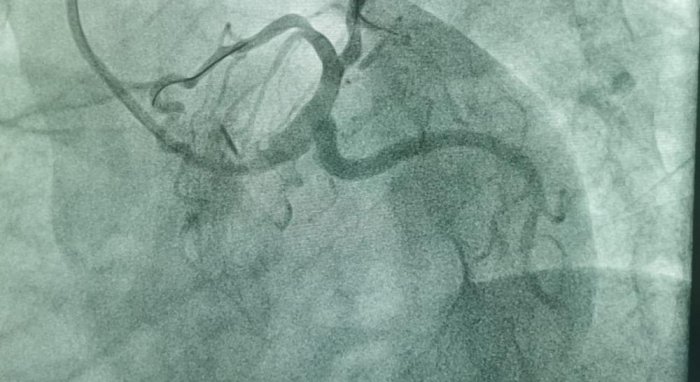

В Мангистауской областной многопрофильной больнице прооперирован пациент с 99% бифуркационным стенозом коронарных артерий. Операция прошла успешно. Об этом сообщили в центре общественных коммуникаций региона.

- Мы провели коронарографию. В результате было выявлено 99% поражения коронарных артерий. Стеноз коронарных артерий – это сужение просвета сосудов, поставляющих кислород и питательные вещества к сердцу, - пояснил врач-аритмолог Курбанали Сабдинов.